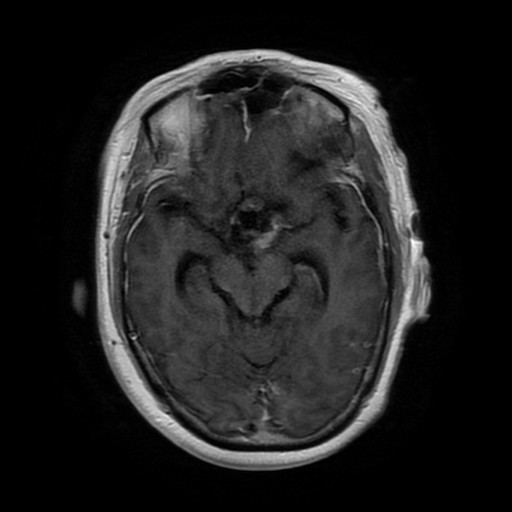

查体:双眼各向视野检查不合作,双侧眼球各向运动灵活,无复视,双侧瞳孔等大等圆,对光反射灵敏,双侧鼻唇沟对称,伸舌偏右,左侧巴氏征可疑阳性。 辅助检查:外院头颅MRA平扫+增强:鞍区巨大含多发囊变肿块(大小约5.6cm*3.8cm*6.6cm),血供稍丰富并包绕左侧大脑前动脉A1段,两侧颈内动脉海绵窦段受压,左侧脑室前角可疑侵犯,性质待定(颅咽管瘤?垂体瘤?其他?);双侧脑室重度扩张积水;双大脑半球部分脑沟信号增高,渗出?少许蛛网膜下腔出血?

诊断:鞍区肿物(性质待查?) 治疗:入院后行头颅MR平扫+增强+MRA示::1、鞍区、鞍上占位,考虑垂体大腺瘤囊变、卒中,突向第三脑室生长,第三脑室、右侧侧脑室扩张,左侧侧脑室受压变窄、移位。2、MRA示脑动脉硬化,右侧颈内动脉、大脑前动脉A1、2段受压移位。遂排除手术禁忌症,于全麻下行“神经内镜辅助下经额鞍区鞍上及脑室内巨大肿物切除术+脑室外引流术”,术后病理示:术后病理示:(鞍区、鞍上及脑室内占位)肿瘤由圆形细胞构成,细胞形态较一致,部分细胞胞浆红染,部分透亮,部分细胞有异型性,核分裂象少见,结合免疫组化及临床,符合垂体腺瘤。 免疫组化结果(②):ACTH(-),PRL(-),TSH(-),FSH(+),GH(-),LH(-),Ki-67(1%~2%+),GFAP(-),CD56(+),CgA(+),Syn(+)。